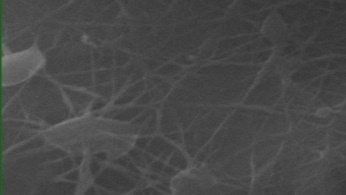

Morphology, size and size distribution of the nanofibres

Morphology analysis was adapted from Aytac et al. (2019) [38]. The SEM analysis was conducted to detect electrospun nanofibers' fibre shape and diameter. The electrospun nanofibres from 18 runs were investigated individually by SEM (FEI, quanta 450, Czech). Images revealed the morphology of resultant nanofibers and measured their diameters in nanometres. The average number of records was calculated using a standard deviation estimation. The setting of the SEM machine was conducted on voltage 25.00 kv, magnification 23624 and width (8.3-9.3 mm).

Results of the SEM analysis are listed in table 2, with a wide range of fibre diameters starting from 87.2 nm (run 13) to 2500 nm (run 18). Run 18 did not produce true nanofibers due to the deficient concentration of PVA. The statistical analysis revealed that the effect of each polymer (factor) on the diameter size of the electrospun nanofiber was vast. Therefore, there is a correlation between factors A, B and C and fibre diameter as expressed in equation 5.

Fig. 3: Nanofibres SEM images with nanofiber diameter frequencies. The PVA, PEO and HPMC were symbolised as V, E and P. Data are given in mean±SD, n=3

The morphology of nanofibers would be affected by device parameters such as flow rate, voltage and distance from the collector. Also, nanofibres' properties could be changed due to temperature and humidity. The bead formation appears with a low concentration of PVA (run 2) or a high concentration of PEO and HPMC (runs 6 and 11), as shown in fig. 3. Therefore, increasing PVA concentration leads to beads' disappearance and smooth fibres' formation. Nageeb El-Helaly (2021) and Silva J. A. et al. (2021) reported similar results [47, 48]. Kalluriet al.(2021)[49] studied the relationship between the fibre diameter, bead diameter and flow rate. Thus, they concluded that better fibre uniformity and bead formation were needed at a high flow rate. These results appear clearly in run two and run six and agree with Silva et al.(2021) results [50], who reported that only the concentration of PVA (≥ 15%) could produce uniform nanofibers when using the lower molecular weight of PVA (67,000). Fibre diameter of 15% PVA and more appeared to be in the range 87.11 to 252.5 nm with uniform fibres and disappearance of beads except in run 6, where the beads appear due to increasing the concentration of HPMC as highlighted by Gripet al. (2018) [46].